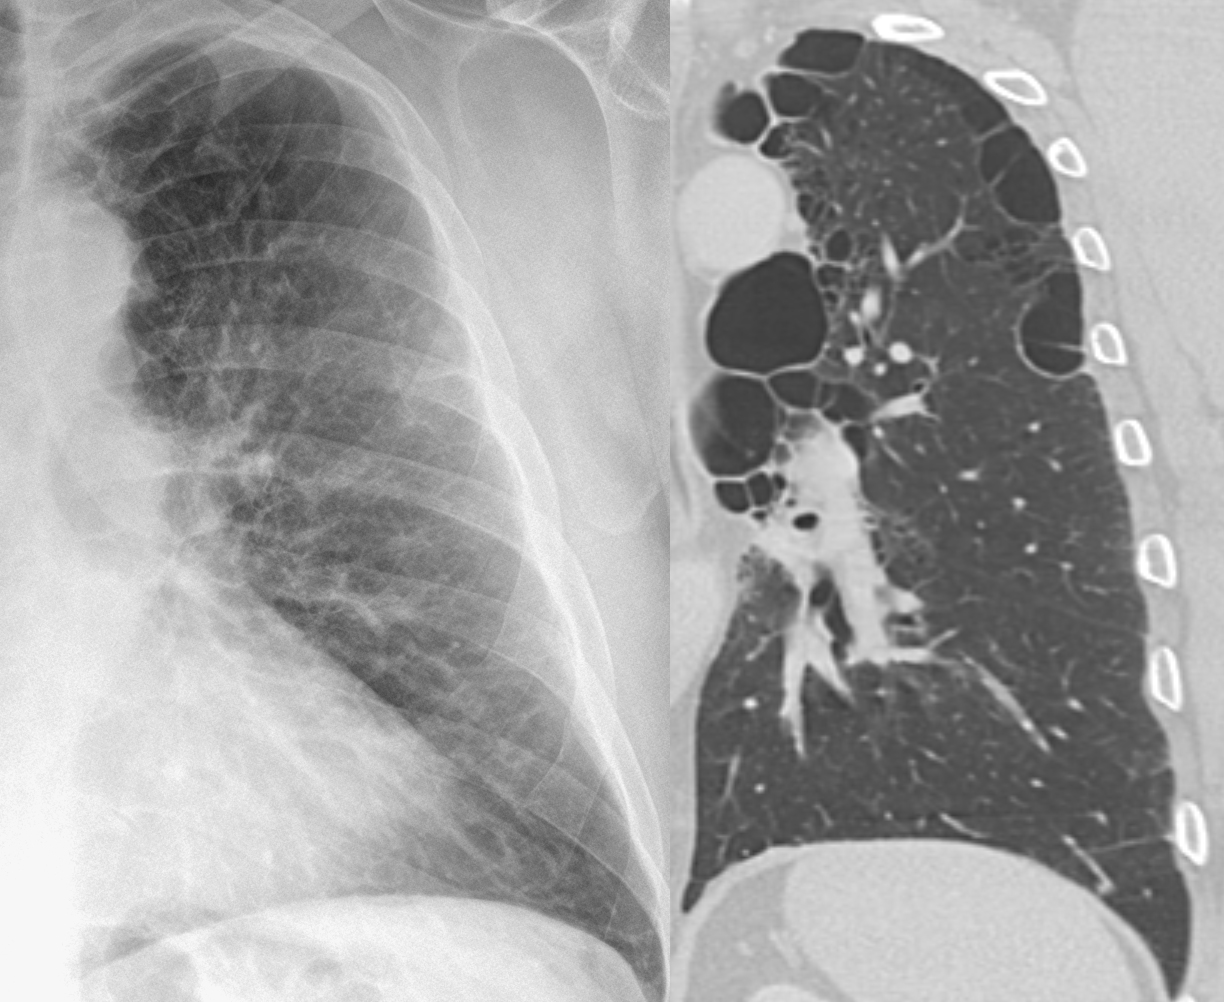

Gallery COPD paraseptal emphysema

paraseptal emphysema